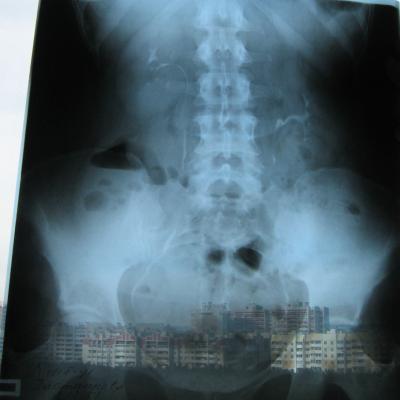

Была сделана операция 04.07.2012г по поводу нефропексии правой почки поясничной мышцей с помощью разреза. После операции болит правая сторона живота и в спине и в пояснице был затронут нерв, и до сих пор правая нога до колен не отходит спереди и сбоку. Через полтора месяца после операции образовался отек, пошло воспаление сзади на спине, потому что был затронут нерв. Сделала урографию через 4 месяца после операции. Если вас не затруднит, посмотрите пожалуйста снимки, правильно ли располагается мочеточник правый после операции. Скажите пожалуйста, посмотрев мои снимки, правильное ли расположение мочеточника и почему болит правая сторона живота все это время, и каким исследованием теперь после операции проверить что там творится в животе, что там затронуто? Все указывает на то что был затронут нерв, оперирующий врач говорит что не может быть такого, а я уже почти всю ногу правую не чувствую

Снимки прикрепляю